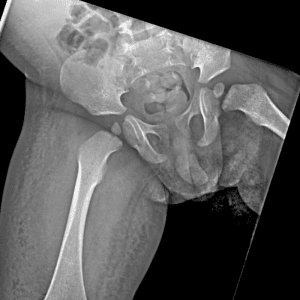

Pediatric Radiographs